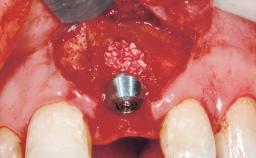

A 42-year-old female patient was referred to our clinic at the School of Dentistry of the University of São Paulo in November 2004, presenting a deficient restoration in the upper left central incisor. The clinical examination revealed no gingival retraction or any signs of gingival inflammation and, therefore, previous periodontal treatment was not considered. The patient presented a high lip line at full smile and a thin tissue biotype. This combination characterized a high-risk situation from an anatomic point of view, which required careful preoperative planning and cautious surgical execution.

Type of Implants One-Piece

Placement Protocol Immediate implant placement

Tooth Site Maxillary incisor or canine

Bone Volume Sufficient, with intact walls